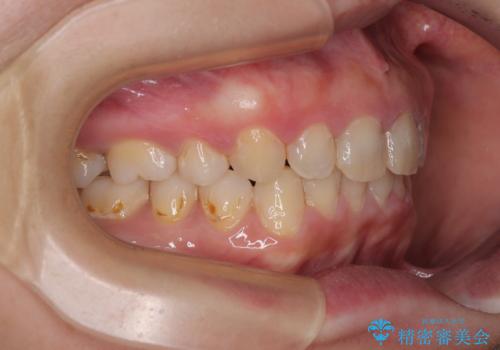

- 上の前歯が出っ歯と突出した口元を気にして来院された患者様です。

上顎歯列全体が前方に飛び出している印象であったので、上顎左右の第一小臼歯2本を抜歯し、ワイヤー装置にて抜歯矯正を行うこととしました。